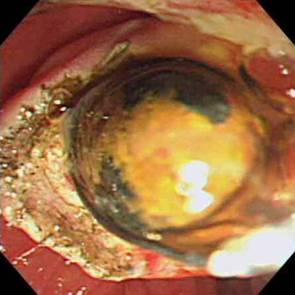

주로 돌이나 종양 때문에 담관이 막혀 염증이 발생하는데 담관염이 확인되면 먼저 응급으로 내시경을 이용하여 (ERCP) 쓸개즙을 배농시켜야하며 때에 따라서 막힌 부위를 뚫어 주어야합니다.

ㆍ담관 결석의 제거

ㆍ췌관결석의 제거